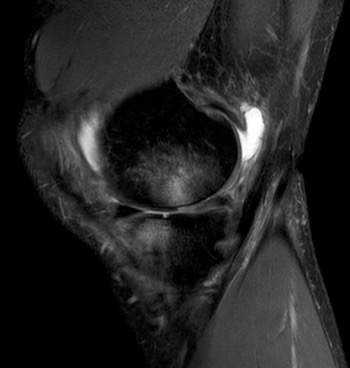

- Das Kernspintomogramm ist stets Teil unserer Analyse. Hier finden sich sektorale Knorpeldefekte innenseitig am rechten Knie sowohl am Oberschenkel als auch am Schienbeinkopf. Die seitliche Aufnahme (rechts) zeigt eindrucksvoll diie Knochenmarködeme an Femur und Tibia (Aufhellungen) als Ausdruck der Überlastung.